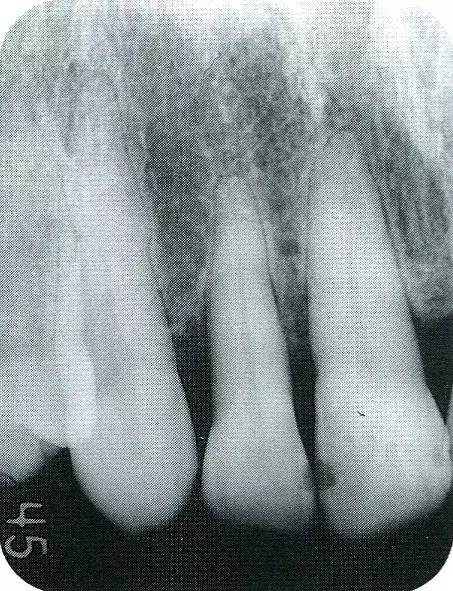

案例3   針對(duì)3壁性垂直性骨缺損使用非吸收性膜進(jìn)行再生治療,再翻瓣時(shí)進(jìn)行骨形態(tài)修整的病例。

▲圖7-1  左下6近中可觀察到3壁性垂直性骨缺損。此病例考慮到齦瓣供血關(guān)系,在前磨牙部位進(jìn)行了減張切開,沒有進(jìn)行縱切開。并利用刮治器、牙周外科用車針進(jìn)行了徹底的骨缺損部位搔刮。